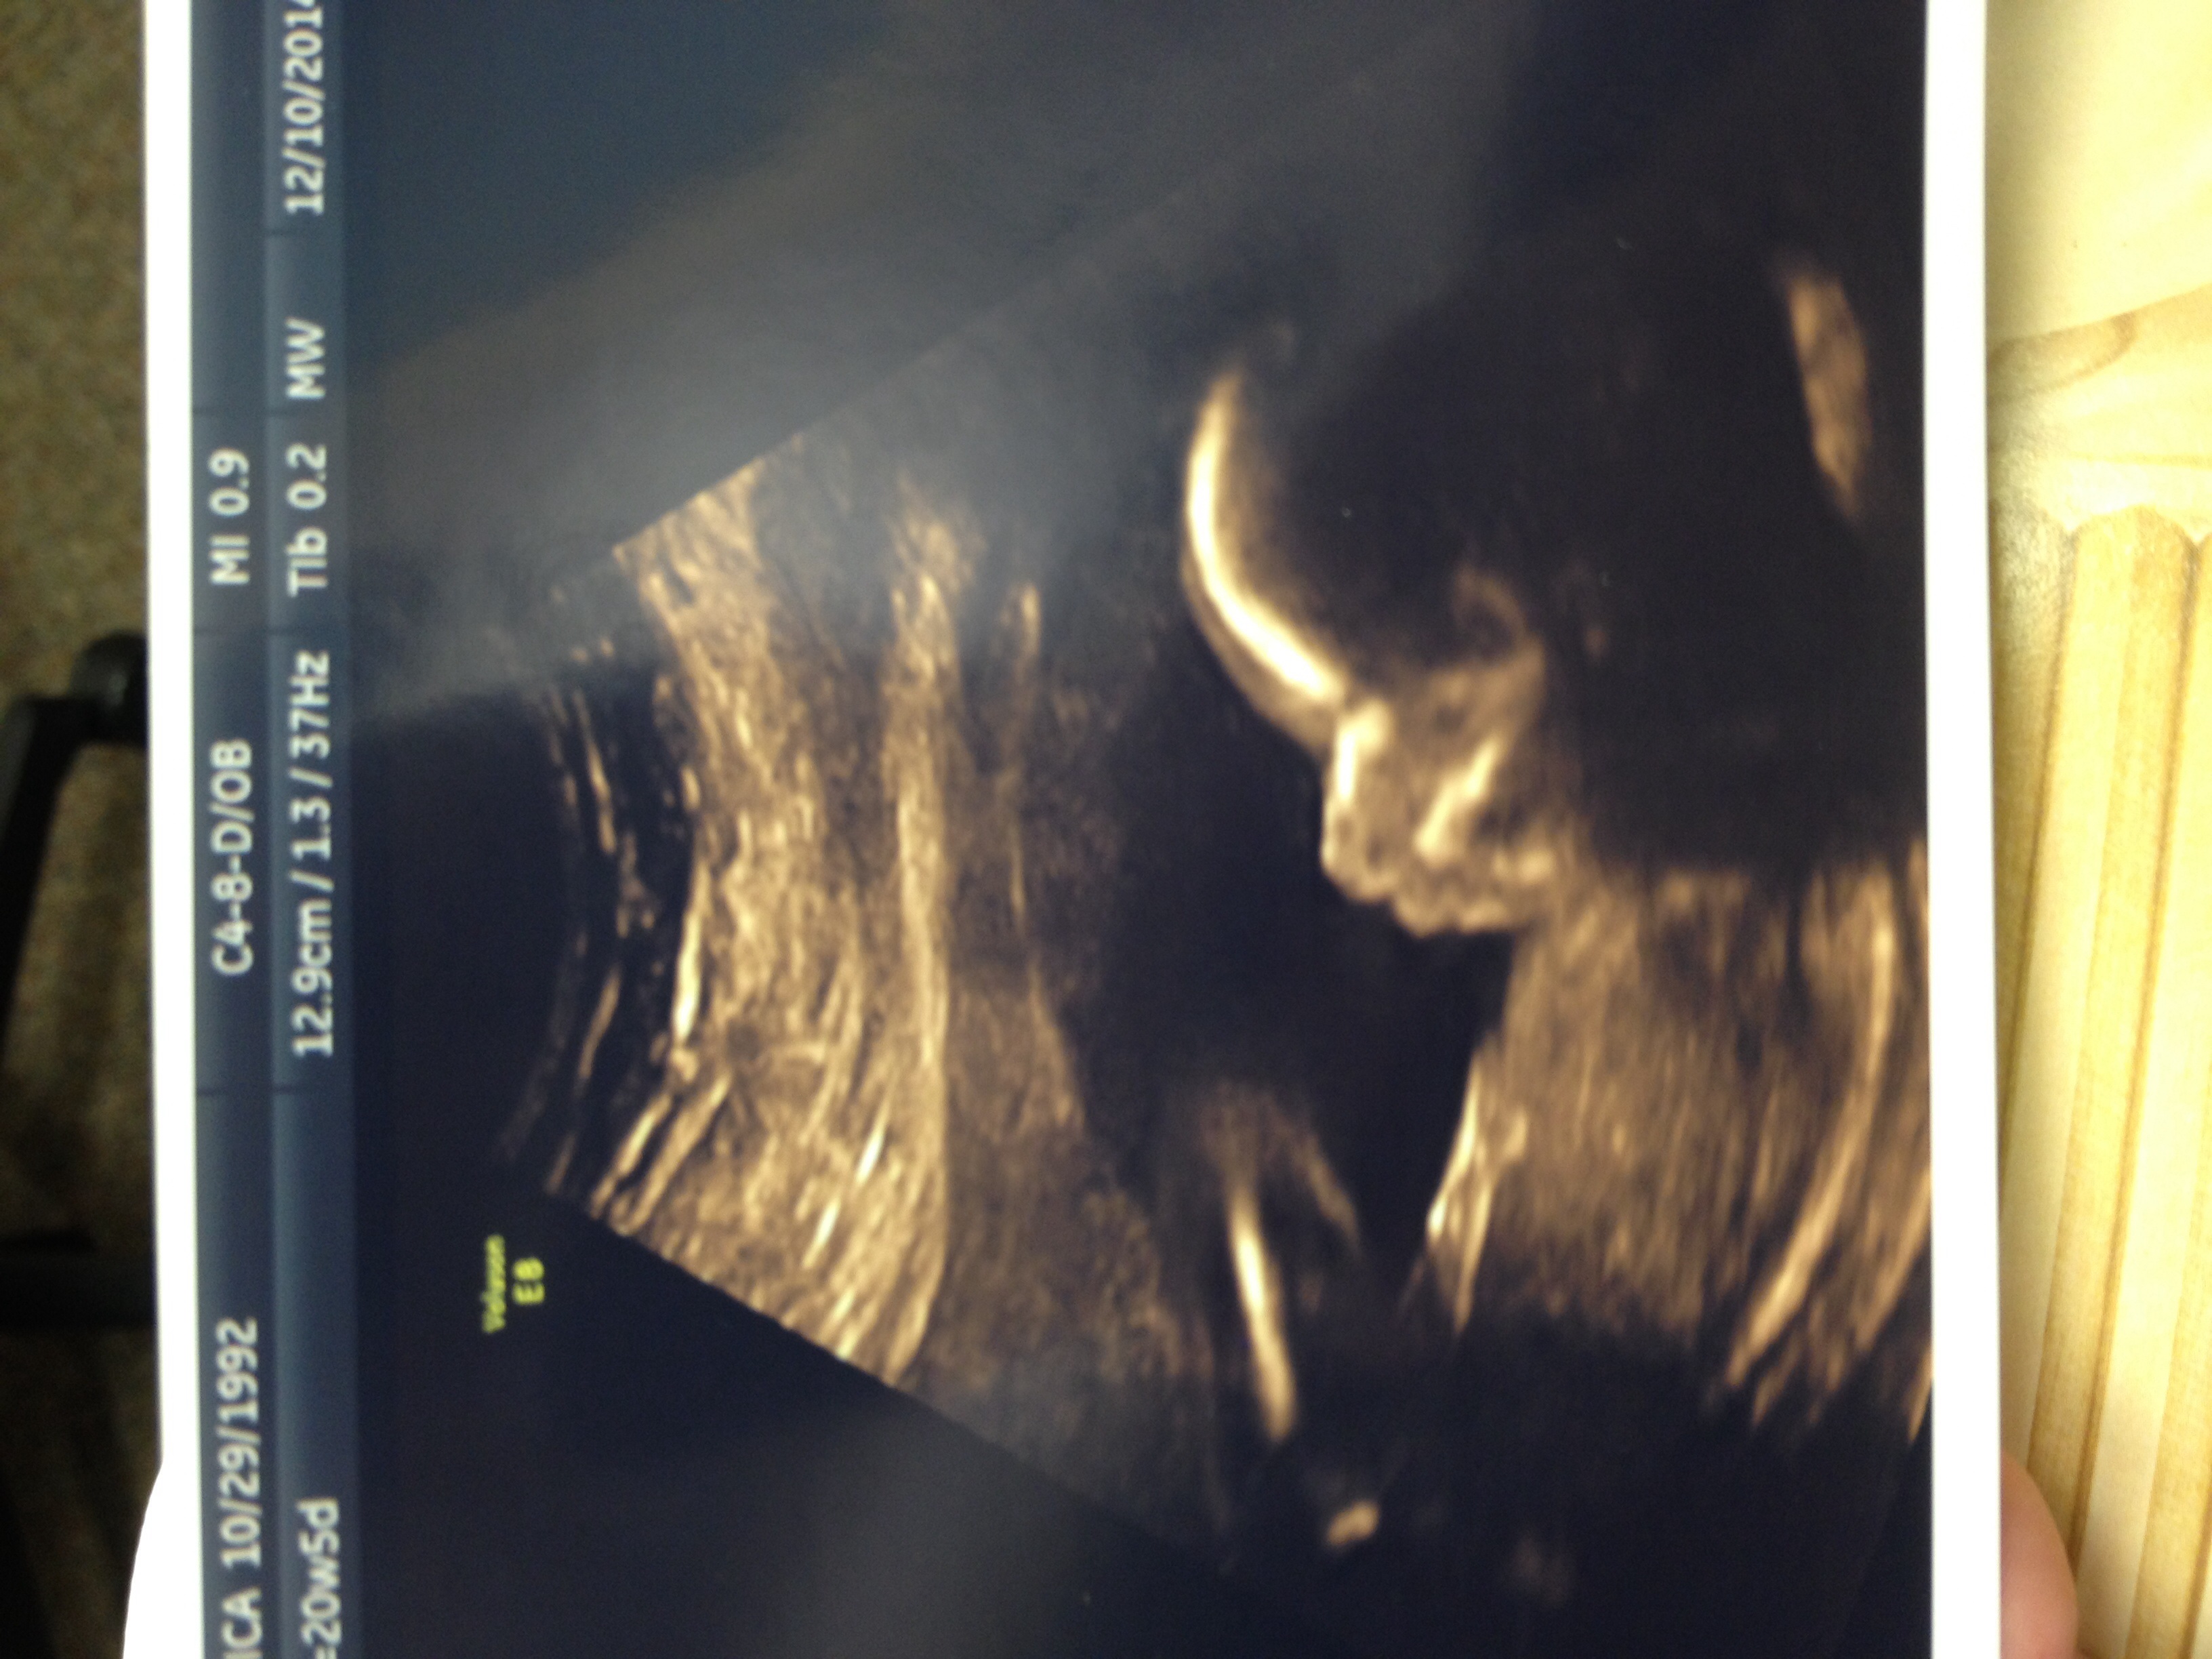

I took this Friday for some family (21w3d) and today I'm 22wks! I wonder why there is not ticker change on Wednesdays...maybe I'll make on next week! You all look fantastic!